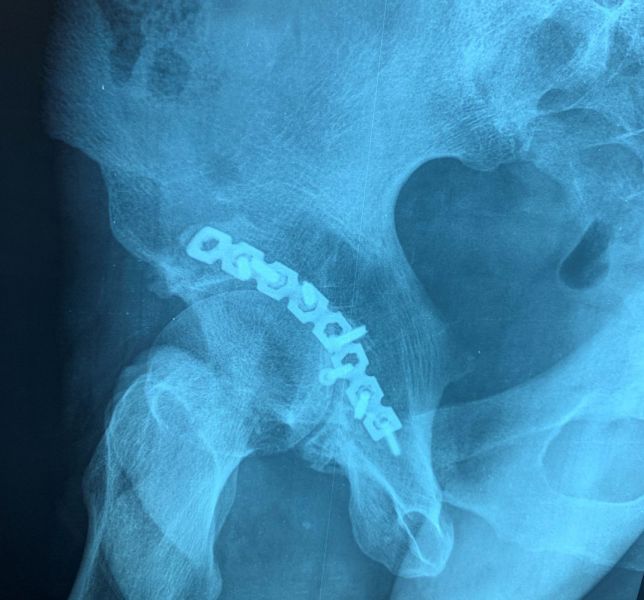

3. Pelvic fracture called also open book fracture in a 27-year-old male.

Treatment: Open reduction internal fixation of pubic symphysis and percutaneous fixation of the left sacroiliac joint

I. Before surgery II. Post-surgery, anteroposterior x-ray of pelvis showing one plate and six screws in pubic symphysis and one large screw in the left sacroiliac joint